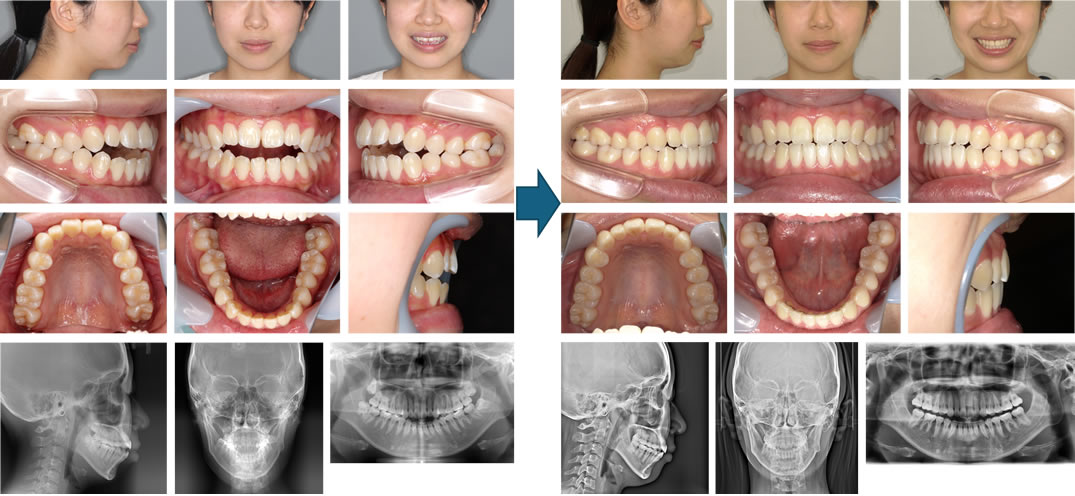

【治療例】初診時年齢:22歳4か月 / 性別:女性 / 主訴:前歯で咬めない、奥歯の負担が大きい、発音しにくい

症例の概要:幼少期に近隣の一般歯科で取り外し可能な装置で受け口の治療をしたが、日に日に開咬を呈してきたという。前歯で咬みきれないこと、発音障害があること、奥歯の負担が大きく、たまに痛みがあることが主訴であったが、舌癖や顔面正中線に対しての下顎骨の左方偏位も認められた。この症例は、マウスピース型(アライナー型)矯正装置(インビザライン®)と顎間ゴムのみで治療し、顔貌も改善した開咬症例である。

主訴: 前歯で咬めない、奥歯の負担が大きい、発音しにくい

診断名: 舌癖と下顎骨の左方偏位を認めた開咬症例

使用した主な装置: マウスピース型(アライナー型)矯正装置(インビザライン®)、顎間ゴム

抜歯/非抜歯および抜歯部位: 非抜歯(IPR)

※こちらの症例は2020年7月から2024年6月に行った矯正です(現在も経過観察中)

治療期間:3年11か月

治療回数:36回

リスクの副作用:歯の移動や抜歯による違和感や疼痛、口内炎、歯肉退縮、歯根吸収が生じることがある